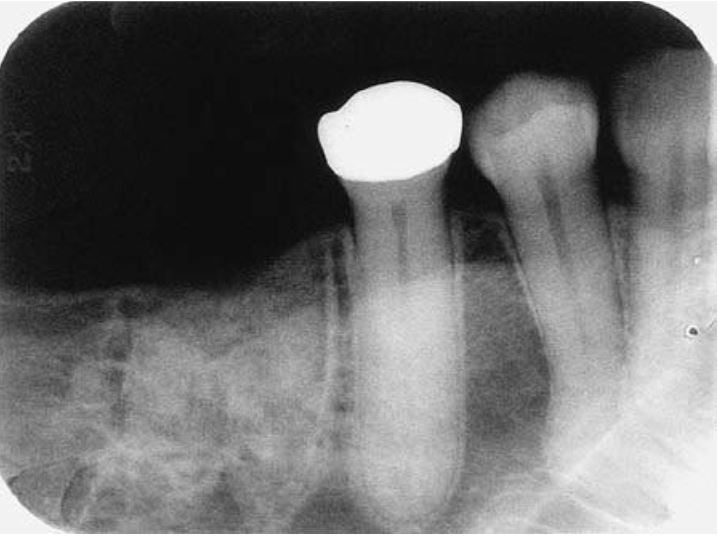

Răng sinh đôi cũng hay có rãnh dọc theo mặt ngoài hoặc mặt trong, khía ở rìa cắn. Trên lâm sàng rất khó chẩn đoán phân biệt giữa răng dung hợp với răng sinh đôi.

Trên phim thì thấy răng sinh đôi chỉ có một buồng tủy rất rộng, chân răng to, thân răng chẻ đôi. Tuy vậy vẫn còn nhiều biến thể khác.